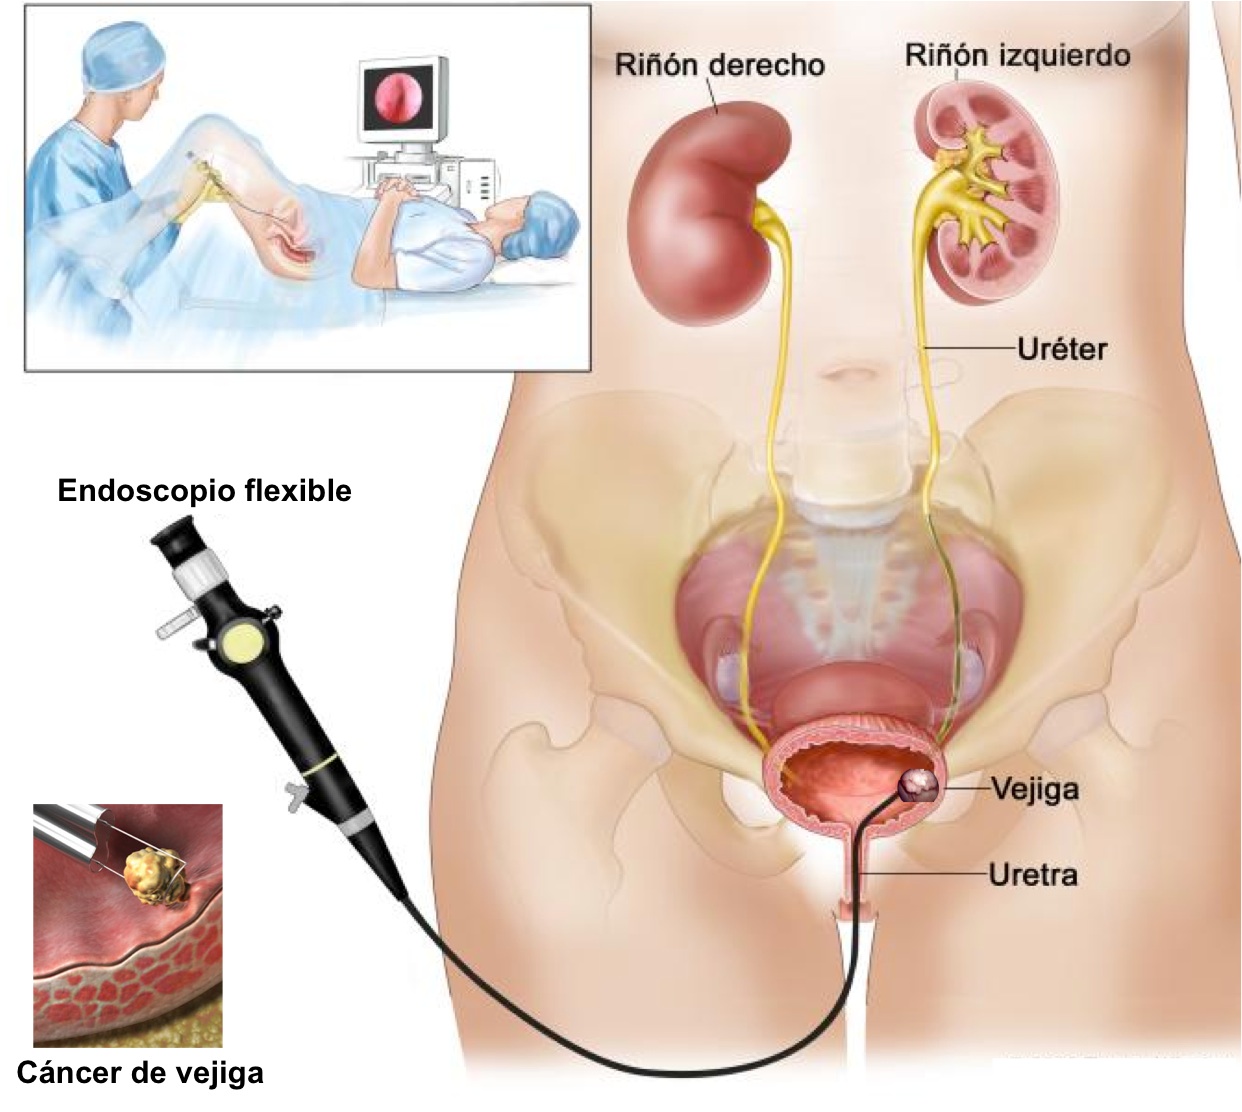

Si se sospecha de la existencia de un tumor, es necesario realizar una exploración denominada cistoscopia, en la que el urólogo observa el interior de la vejiga a través de la uretra, con un instrumento denominado cistoscopio.

Hoy día existen modernos instrumentos flexibles que permiten realizar esta exploración de forma indolora, incluso sin necesidad de anestesia.

La intervención inicial es la Resección TransUretral (R.T.U.) para extirpar y analizar el tumor.

Es una cirugía poco agresiva, realizada a través del orificio natural de la uretra, con alta hospitalaria en 24-48 horas.